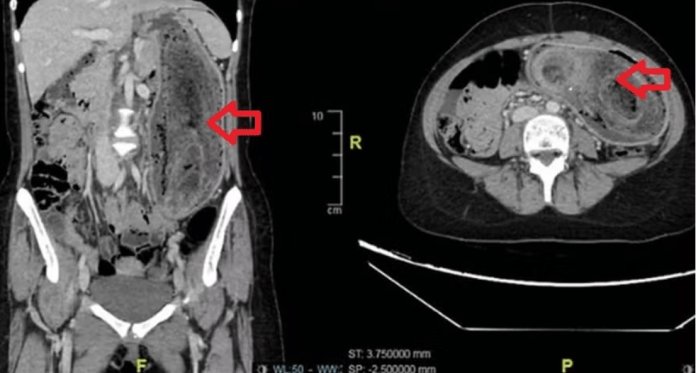

Durante a avaliação, os médicos notaram que o abdômen estava inchado, dolorido e apresentava uma massa endurecida ao toque. Exames de imagem confirmaram a suspeita: havia um aglomerado de cabelo ocupando todo o estômago e se estendendo até o duodeno, quadro típico da síndrome.

Como a massa era muito volumosa, não foi possível removê-la por endoscopia. A equipe optou por uma cirurgia aberta, realizada sob anestesia geral. O procedimento durou cerca de três horas e permitiu a retirada da bola de cabelo de forma intacta.